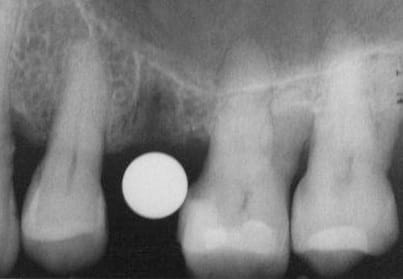

merci pour tes réponses, pour ma part (expérience avec plus de 600 implantation immédiate) je ne pense pas qu'il va y avoir une résorption, car pas de lambeau et tu n'as pas mis de trop grande pression sur l'os buccal.Un exemple ci dessous implantation ( 4 semaines après extraction) avec un 4.5 que (oui déjà mis dans un autre post).J'ai d'autres exemples similaires en extraction implantation immédiate mais avec des implants 3.5mm.Si l'espace entre l'implant et l'os buccal est plus grand que 1mm j'ajoute du collagène et de l'acide hyaluronique pour accélérer la régénération.

dernière radio à un an après cémentation de la couronne.

Ce qui est non négligeable est d'avoir une stabilité primaire d'un minimum de 35Ncm et pas plus de 70Ncm.